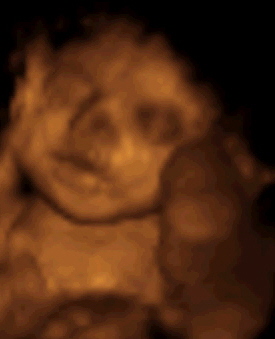

Annyira édes a pici Kincső. Nekem is már csak egy hét az UH-ig. Igaz az csak sima 2D-s, de nálunk nagyon drága a 4D-s UH, de még ha lenne is rá, akkor is legalább 2 hónap az előjegyzés, addigra meg már meszületik, mert ugyi most kérhetnénk karácsonyra, de most már nem érdemes.